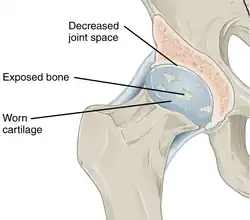

Annotated illustration of healthy hip joint

Healthy hip joint

Annotated illustration of hip joint with osteoarthritis

Hip joint with osteoarthritis[36]